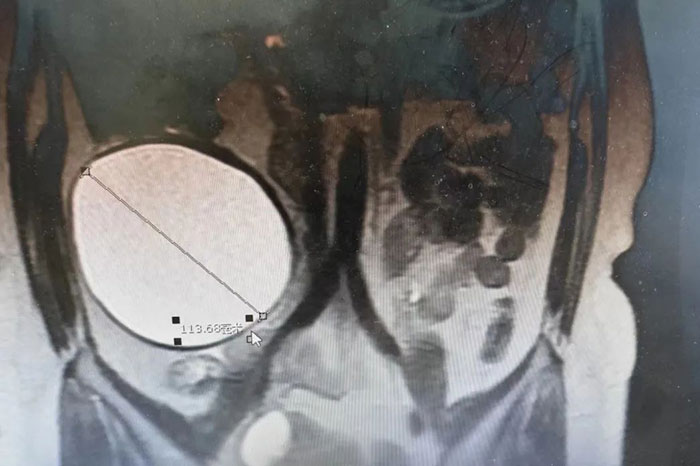

近日,滄州市中心醫(yī)院河間分院肝膽外科(外一科)、婦科、麻醉科通力合作共同協(xié)作成功為一女性患者切除將近13厘米大小的巨大腹膜后腫瘤,聯(lián)合右半結(jié)腸切除術(shù)。通過多學(xué)科協(xié)作治療,再次彰顯滄州市中心醫(yī)院河間分院外科技術(shù)實力。

患者腫瘤位于升結(jié)腸后方,體積巨大,上至結(jié)腸肝區(qū),下至盆腔入口處,擠壓升結(jié)腸向腹部正中內(nèi)側(cè)推移,質(zhì)地硬,有完整包膜,前方與升結(jié)腸系膜融合,未浸透漿膜層,無法分離。同時患者右側(cè)卵巢內(nèi)存在一個直徑5厘米的囊性腫物。